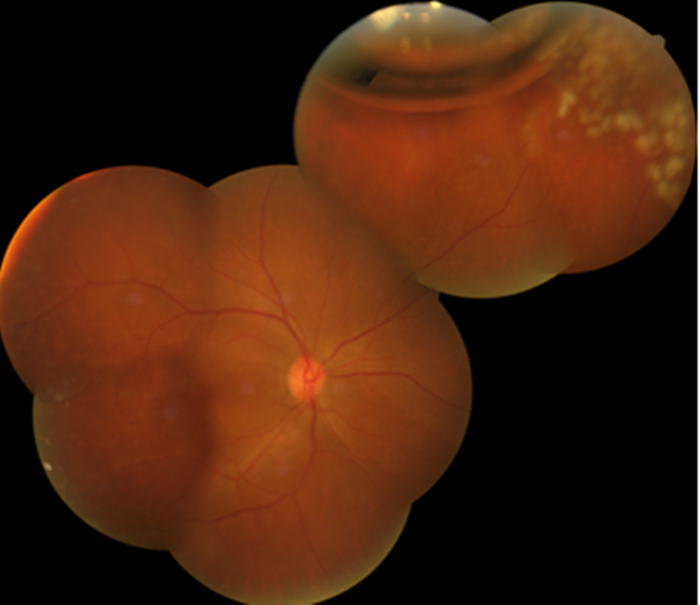

眼底檢查術前

眼底檢查術后